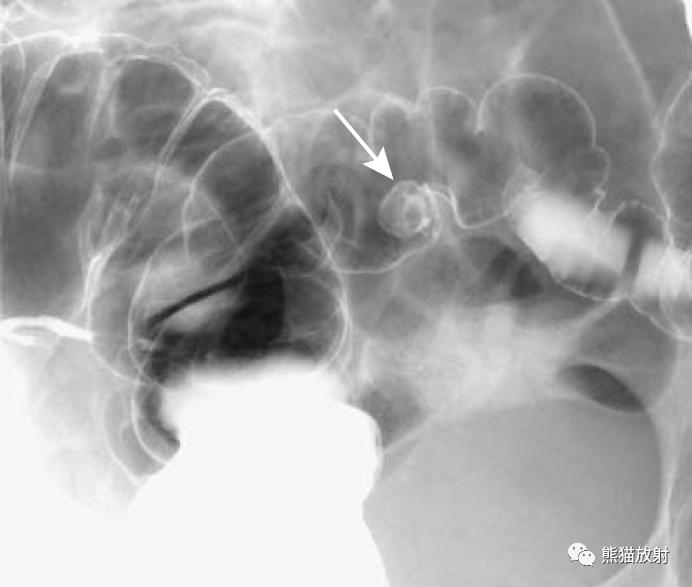

乙状结肠腺癌(箭头)。1cm圆形肿瘤,边缘光滑,其内的小圆圈是肿瘤的蒂。